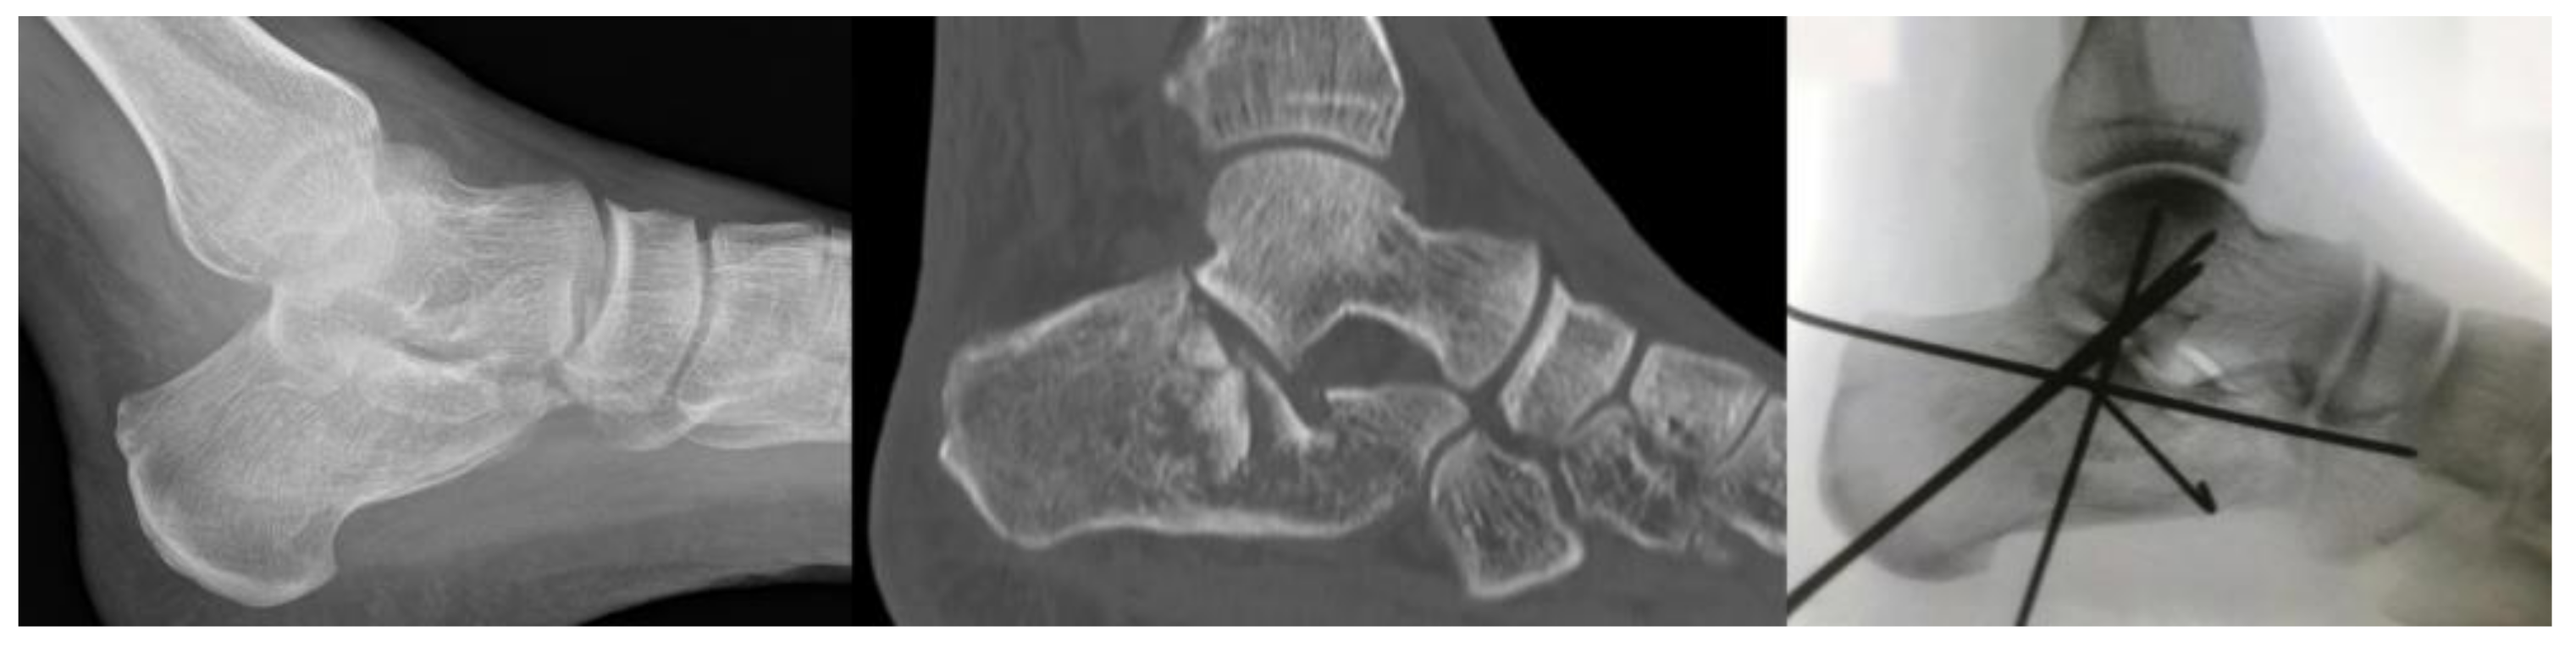

Pre-operative X-rays showed a tongue type fracture pattern in 14 (42.4%) patients, while a joint depression type was reported in the remaining 19 (57.6%) cases (Figure 2).

Figure 2.

Left: pre-operative lateral X-Ray. Middle: pre-operative CT scan showing the IACF with severe joint depression. Right: postoperative lateral X-Ray showing good reduction stabilized with K-Wires.